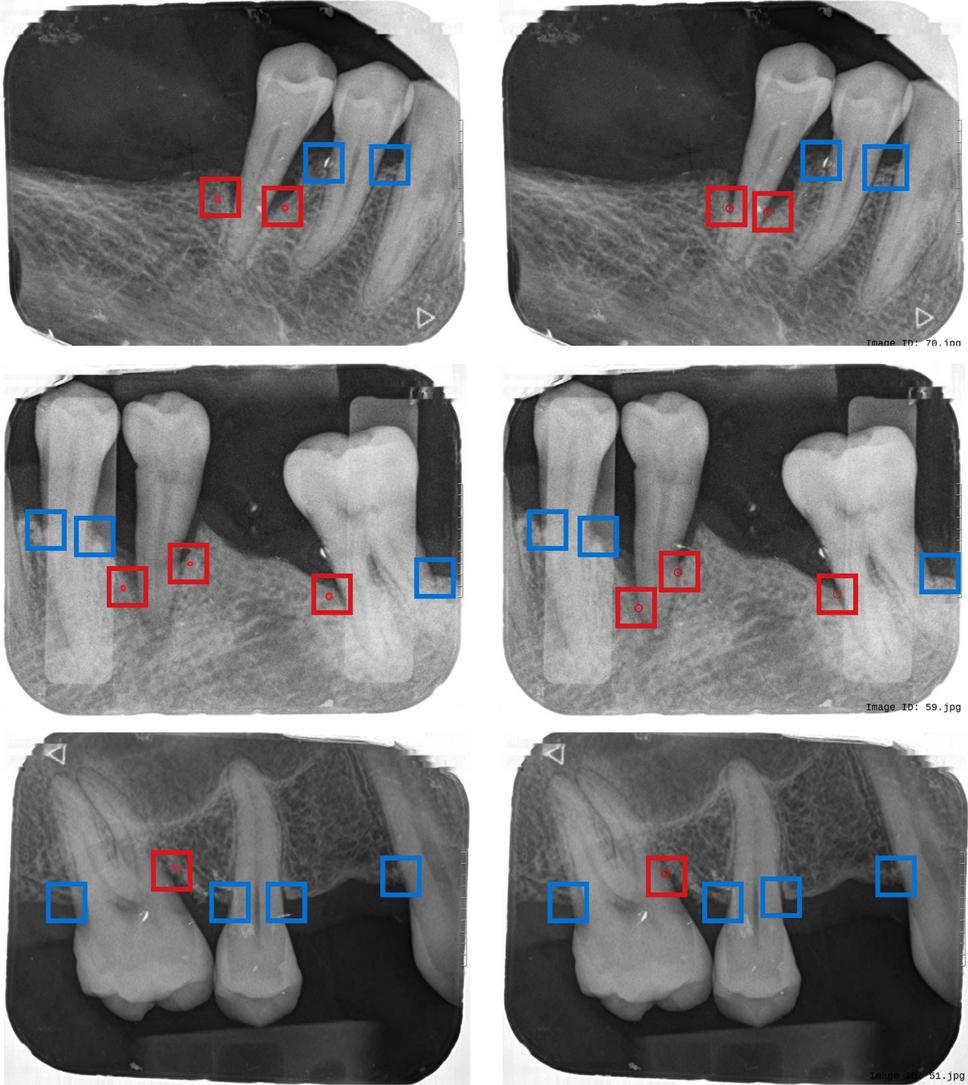

Fig. 12

From: AI-assisted radiographic analysis in detecting alveolar bone-loss severity and patterns

Comparison of bone loss patterns between ground truth (left) and predicted results (right). Red small circles indicate angular bone loss cases predicted by the system. The red rectangle highlights angular bone loss cases, while the blue rectangle highlights horizontal bone loss cases.